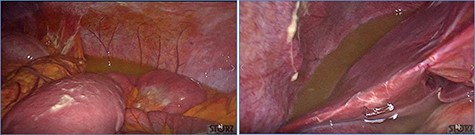

Diffuse exudative fluid and fibrin clots at laparoscopic exploration: (a) left upper quadrant and (b) right upper quadrant.

fluid collection in the peritoneal cavity. Subsequent CT confirmed the presence of diffuse fluid collection in the peritoneal cavity (Fig. 1) but no free air, with distention, bundling and thickening of some small bowel in the left quadrant (Fig. 2). The patient was therefore admitted for supporting therapy (intravenous fluids and antibiotics) with the suspicion of cocaine-induced small bowel ischemia. Twelve hours later, signs and symptoms of diffuse peritonitis developed: worsening diffuse abdominal pain with rebound guarding at examination, a significant increase in WBCs count (16.15 × 103/μl) and neutrophilia (88%), lengthening of coagulation times (INR: 1.68; aPTT: 33.0 s) and increase in fibrinogen (430 mg/dl) and D-Dimer (2275 ng/ml). Therefore, urgent surgical exploration of the abdomen through a three-port open laparoscopic approach was performed, confirming the presence of 1200 ml of exudative fluid and fibrin clots (Fig. 3). Several adhesions between greater omentum, abdominal wall and small bowel underwent blunt dissection. Thorough exploration of the small bowel revealed two ischemic segments located at about 50 and 100 cm from the Treitz ligament (Fig. 4). The large bowel appeared normal. The existence of non-visible gastro-duodenal perforations was ruled out with the administration of 500 ml of saline with 20 ml of methylene blue through the nasogastric tube. An iv bolus of sodium heparin, 10 000 IU, was then administered, performing a 30-min peritoneal lavage with 5 l of saline solution at 37°C. After reaspiration of peritoneal lavage, a new complete exploration of the small bowel was performed, showing complete revascularization of the two ischemic small bowel segments (Fig. 5). Two tubular drainage tubes were placed in the left and right colic gutters. Culture examination of peritoneal exudate was positive for multi-sensitive Escherichia coli and Enterococcus, thus confirming bacterial translocation peritonitis. Postoperative therapy included the administration of iv piperacillin–tazobactam and subcutaneous low molecular weight heparin. Postoperative recovery was smooth, with oral feeding on the second postoperative day (POD), drainage removal on POD 3, complete bowel function restored on POD 4 and home discharge on POD 5. At 15- and 30-day-follow-up, the patient showed full recovery, being now followed by a specialized support structure for his drug abuse.